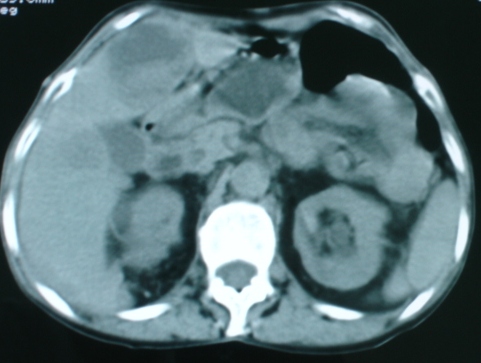

以下是引用zsl6918在2008-11-4 19:14:00的发言:[br]多发转移性改变,子宫改变不除外为原发灶